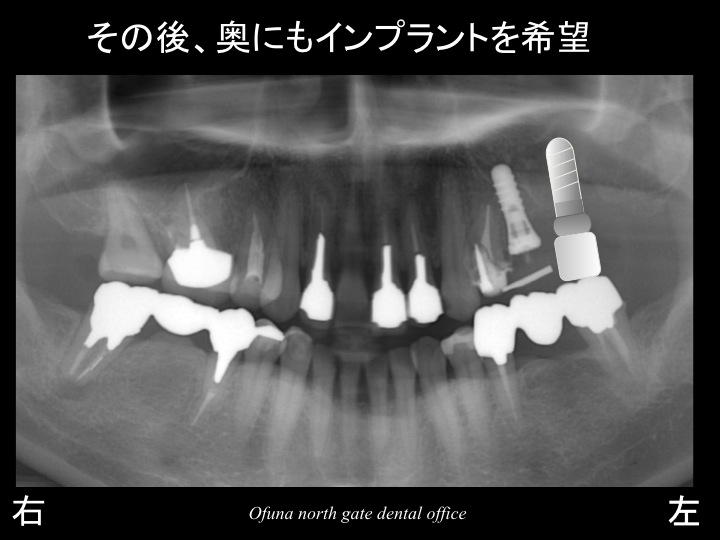

奥にインプラントを埋入したのが以下になります。

今度は、奥のインプラントと骨が結合するまで さらに4ヶ月程度待つ必要性があります。

その間は、以下のような仮歯を使用します。

以下のレントゲンは、治療前の上顎洞 と 治療後の上顎洞の位置の比較です。

緑線は、治療前の上顎洞です。

黄色線は、現在の上顎洞です。

サイナスリフト法(上顎底挙上術) によって大幅に骨の増大が可能になりました。